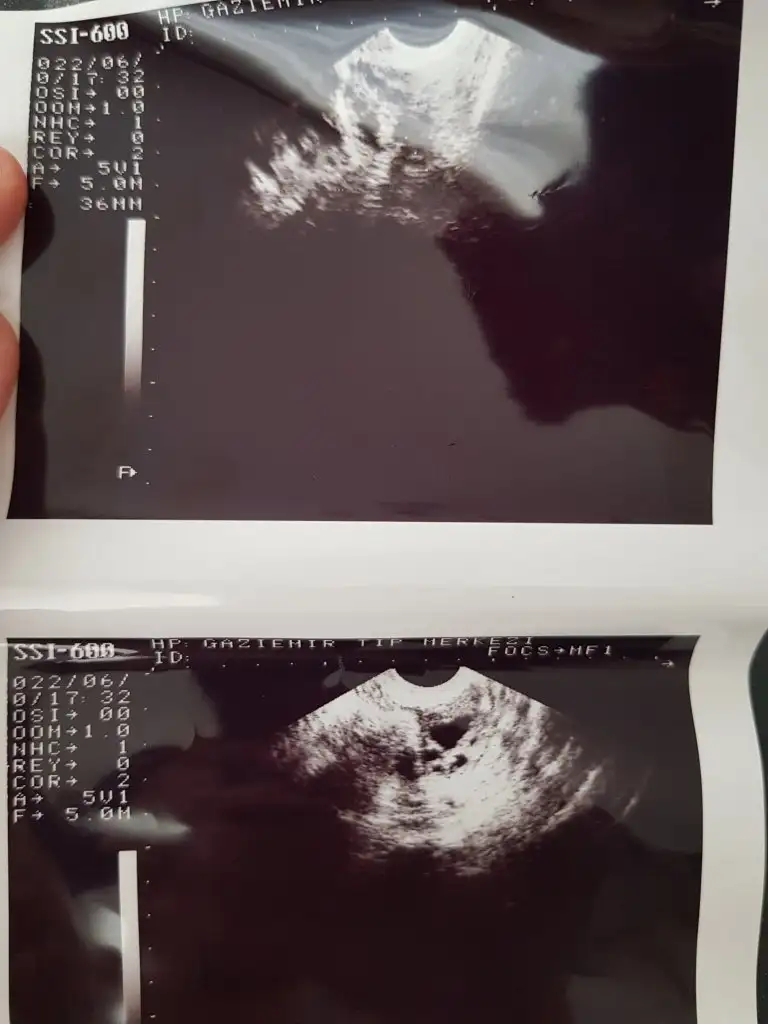

Dün de ultrasona girdim keseyi de gördüm çok şükür şuan her şey yolunda

5+6 haftalıgız